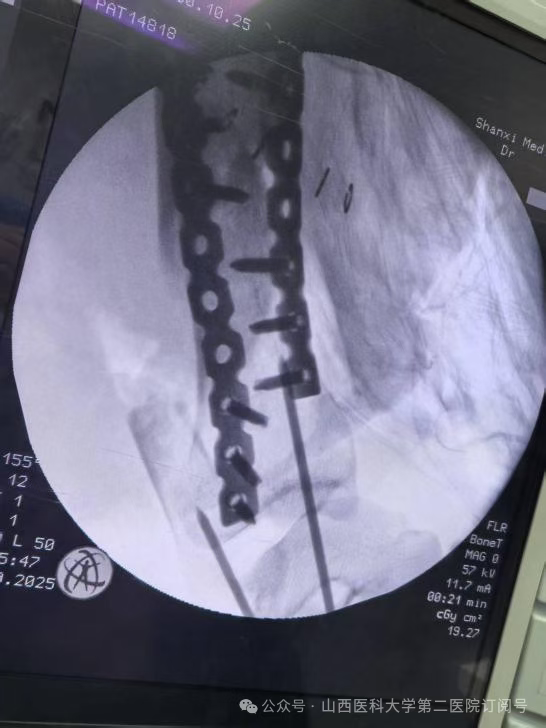

手术台上,每一步都至关重要。在总住院张桦栋医师、显微手外科董建峰主任、王怀刚医师的带领下,手术团队展现了高超的骨显微外科技术。精确地分离、保护重要的神经和血管,确保移植肢体的血供;在毫米之间进行骨骼的截除与重塑;将肌肉、肌腱等软组织进行精确对位缝合,以重建动力系统。整个手术过程犹如在显微镜下雕琢一件生命艺术品。麻醉科张林忠主任、贺萱医师主持麻醉,手术室田小荣护士长,霍元玲、刘萍护师熟练配合历时六小时,最终圆满成功,患者股动脉的血液源源不断地重新滋养左足。术后,患者生命体征平稳,移植的足部血运良好。

骨科总住院医师张桦栋医师介绍:“这个手术的理念堪称重塑。其核心原理是将受损严重的左小腿部分及左膝切除,保留功能完好的足部,并将其旋转180度后,与大腿股骨进行固定融合。这样一来,原本的踝关节就扮演起了膝关节的角色。形象地说,这就像进行了一次精密的“人体拼装”:将脚踝调转方向,与大腿连接。术后,通过专业的康复训练,患者可以利用这个“新的膝关节”(即原来的踝关节)进行屈伸活动,从而驱动假肢,实现更自然、更有力的行走。这远比传统大腿截肢后佩戴的假肢功能更优,能量消耗更少,步态也更接近正常人。